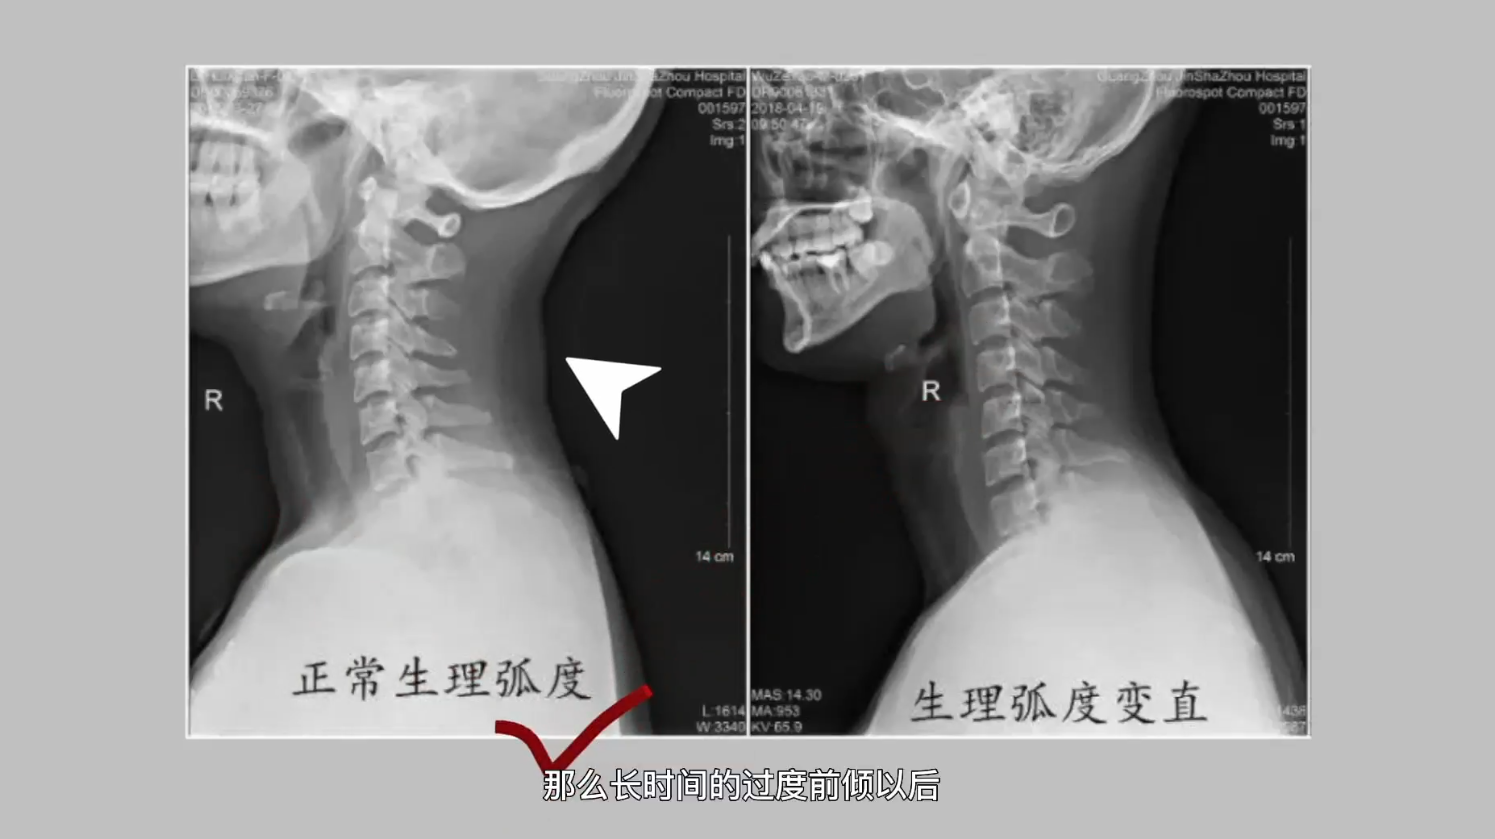

脊柱是由颈椎、胸椎、腰椎、骶椎、尾椎共32个椎体,通过23个富有弹性的椎间盘和很多活动方向不同的小关节,以及长短不等的坚强韧带连结而成的。它上连颅骨,中部与肋骨相连,下端和髋骨组成骨盆。正常人的脊柱自上而下有4个像弹簧样的生理弯曲,从侧面看呈S形,即颈椎前凸、胸椎后凸、腰椎前凸和骶椎后凸。